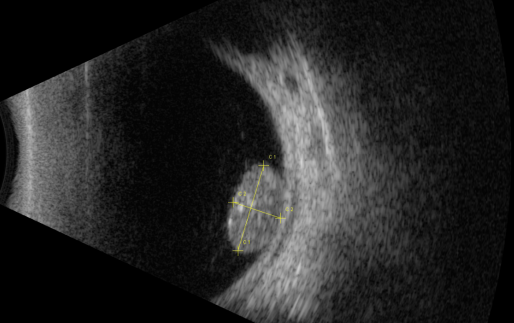

視網膜母細胞瘤是嬰幼兒常見的眼內惡性腫瘤,可危害患者的視力、眼球和生命。其惡性程度高,多發(fā)于兒童,尤其是3歲以下的兒童,常表現為白瞳癥,可侵及單眼或雙眼。

根據腫瘤的表現和發(fā)展過程可分為眼內期、青光眼期、眼外期和全身轉移期。

1、眼內期

開始在眼內生長時外眼正常,因患兒年齡小,不能自述有無視力障礙,因此本病早期一般不易被家長發(fā)現。當腫瘤增殖突入玻璃體或接近晶體時,瞳孔區(qū)出現黃白色反光,如貓眼樣(“黑貓眼”),此時常因視力障礙而瞳孔散大、白瞳癥或斜視被家長發(fā)現。